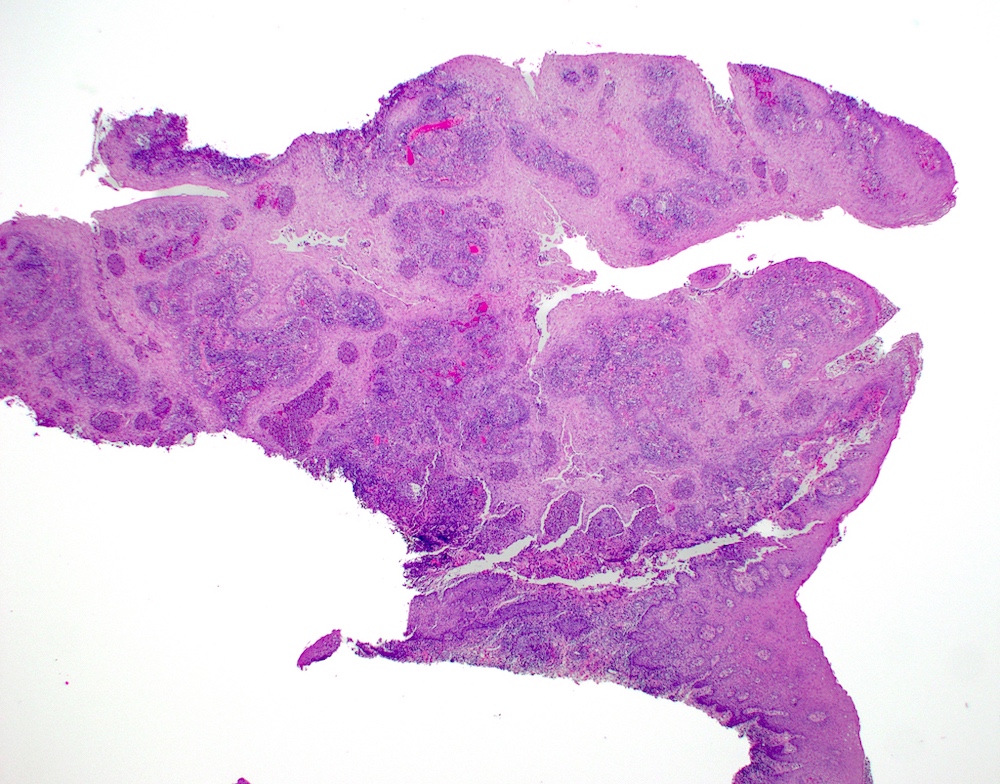

Microscopic (histologic) images

Contributed by Molly Housley Smith, D.M.D.

PEH in granular cell tumor PEH in granular cell tumor

PEH in granular cell tumor

B. Granular cell tumor with overlying pseudoepitheliomatous hyperplasia (PEH). Microscopic sections show a dome shaped mass of pale, basophilic, plump granular cells surfaced by hyperkeratotic and hyperplastic epithelium. Although the rete ridges are significantly proliferative and demonstrate keratin pearls, overt cytologic atypia is not appreciated. This proliferative pattern of the epithelium is termed pseudoepitheliomatous hyperplasia and is known to be associated with granular cell tumors. Answer A is incorrect because although there is a thickened layer of parakeratin, this answer choice ignores the replacement of the fibrous stroma by plump granular cells. Answer C, a common pitfall in the diagnosis of this tumor, is incorrect because although the epithelium is proliferative, prominent cytologic atypia is not appreciated. The pathologist must be keen in recognizing the underlying replacement of the fibrous stroma with plump granular cells and must know that granular cell tumors characteristically show PEH in many cases. Answer D is incorrect because verrucous carcinoma would show keratin clefting and prominent, bulbous, plunging rete ridges that push into the underlying muscle.